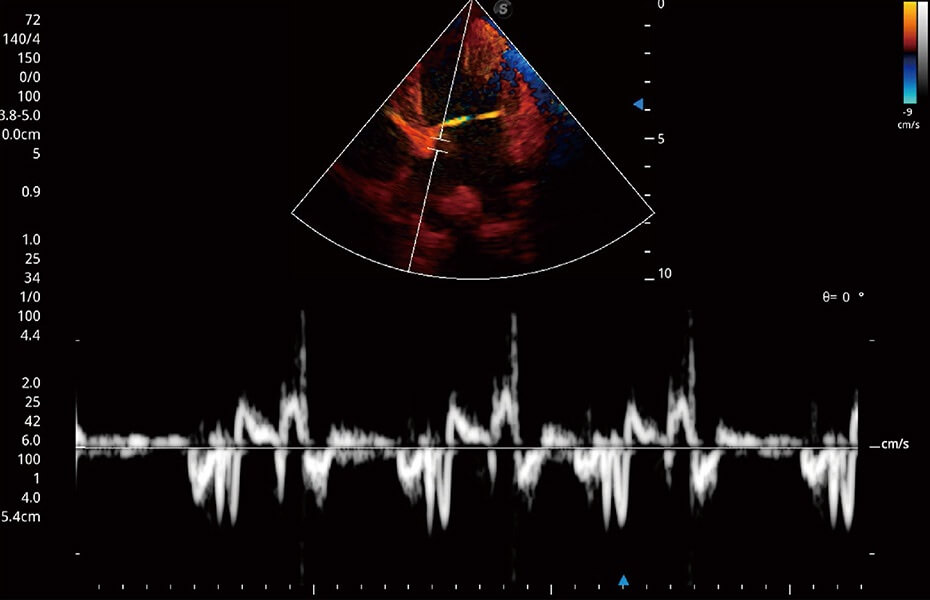

ProPet 60 作為一款高端臺(tái)式動(dòng)物超聲設(shè)備,為動(dòng)物醫(yī)生的日常診斷提供了一系列貼合動(dòng)物臨床需求、解決臨床實(shí)際問題的高級成像功能。憑借全系列高清探頭,滿足醫(yī)生對腹部、心臟、生殖、淺表、肌骨等成像的所有需求,切實(shí)幫助您提升檢查效率,提高診斷信心。